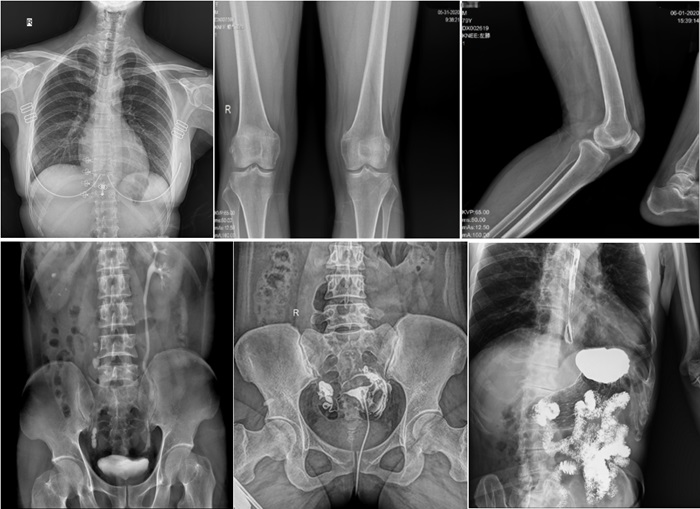

在實際應用中,普利德動態(tài)平板DRF展現(xiàn)出了多種優(yōu)勢。例如,在胸部影像檢查中,它清晰顯示肺部紋理和結節(jié),為肺癌早期篩查提供有力支持;在骨科領域,可用于骨折的診斷和復位效果評估,幫助醫(yī)生制定更精準的治療方案;在消化系統(tǒng)檢查中,能有效發(fā)現(xiàn)胃腸道疾病的異常。

在婦科方面,不僅能夠直觀的觀察子宮形態(tài)、大小,輸卵管各部有無扭曲、管腔粘連以及梗塞情況,還可以在加壓推注下,使部分輸卵管輕、中度堵塞的患者得以通暢,起到有效的治療作用。